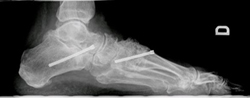

- Osteotomías (correcciones óseas)

- Artrodesis (fijación de articulaciones).